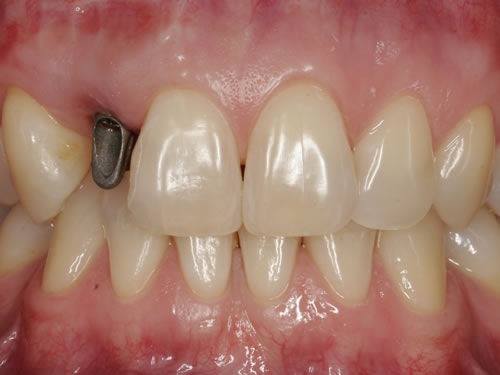

Häufig führt ein Zahnverlust zu einem Verlust von Knochen (Hartgewebe) und der bedeckenden Schleimhaut (Weichgewebe). Besonders im sichtbaren ästhetisch sensiblen Bereich ist es aber notwendig, dass sowohl Hart- als auch Weichgewebe so wiederhergestellt wird, dass im Idealfall das Zahnimplantat mit seiner Krone dem Aussehen des ehemaligen gesunden Zahn entspricht. Als Erfolgskriterien werden aus zahntechnischer Sicht die Form, Farbe und Größe der individuellen Krone angesehen. Aus medizinischer Sicht gibt es wichtige Erfolgskriterien, die die Implantatposition, die Implantatlänge, den Implantatdurchmesser, den Zahnfleischrand im Vergleich zum Nachbarzahn und die Zahnfleischpapillen zwischen den Zähnen beinhalten. Zusätzlich braucht man ein zahntechnisches Labor, das mit der Keramikverarbeitung ein natürliches Aussehen gestalten kann. Nur, wenn alle Parameter perfekt sind, ist das Ergebnis perfekt. Das macht den Einzelzahnersatz im Oberkieferfrontzahngebiet zu einer echten Herausforderung.

Nach der Entfernung von Zähnen kommt es schnell zu Knochenverlust (Resorptionen) und entsprechendem Verlust von Schleimhaut. Die Schleimhaut kann durch bestimmte Operationstechniken wiederhergestellt werden, in dem man freie oder gestielte Bindegewebstransplantate z. B. vom Gaumen entnimmt und das fehlende Material so ersetzt. Das Weichgewebe kann in unterschiedlichen Behandlungsphasen korrigiert werden. In vielen Fällen wird es während der Implantation oder bei der Freilegung verbessert. Manchmal müssen Feinkorrekturen auch nach Eingliederung der fertig gestellten Krone erfolgen, wenn ästhetische Einbußen vorliegen. Häufig hat die Zahnfleischkorrektur auch noch einmal die Änderung der endgültigen Krone zur Folge (Abb. 7.14, 7.15).

Abb. 7.14: Unbefriedigendes ästhetisches Ergebnis nach Implantatversorgung.

Abb. 7.15: Perfektes Ergebnis nach Weichgewebskorrektur und nach Eingliederung der geänderten Krone.